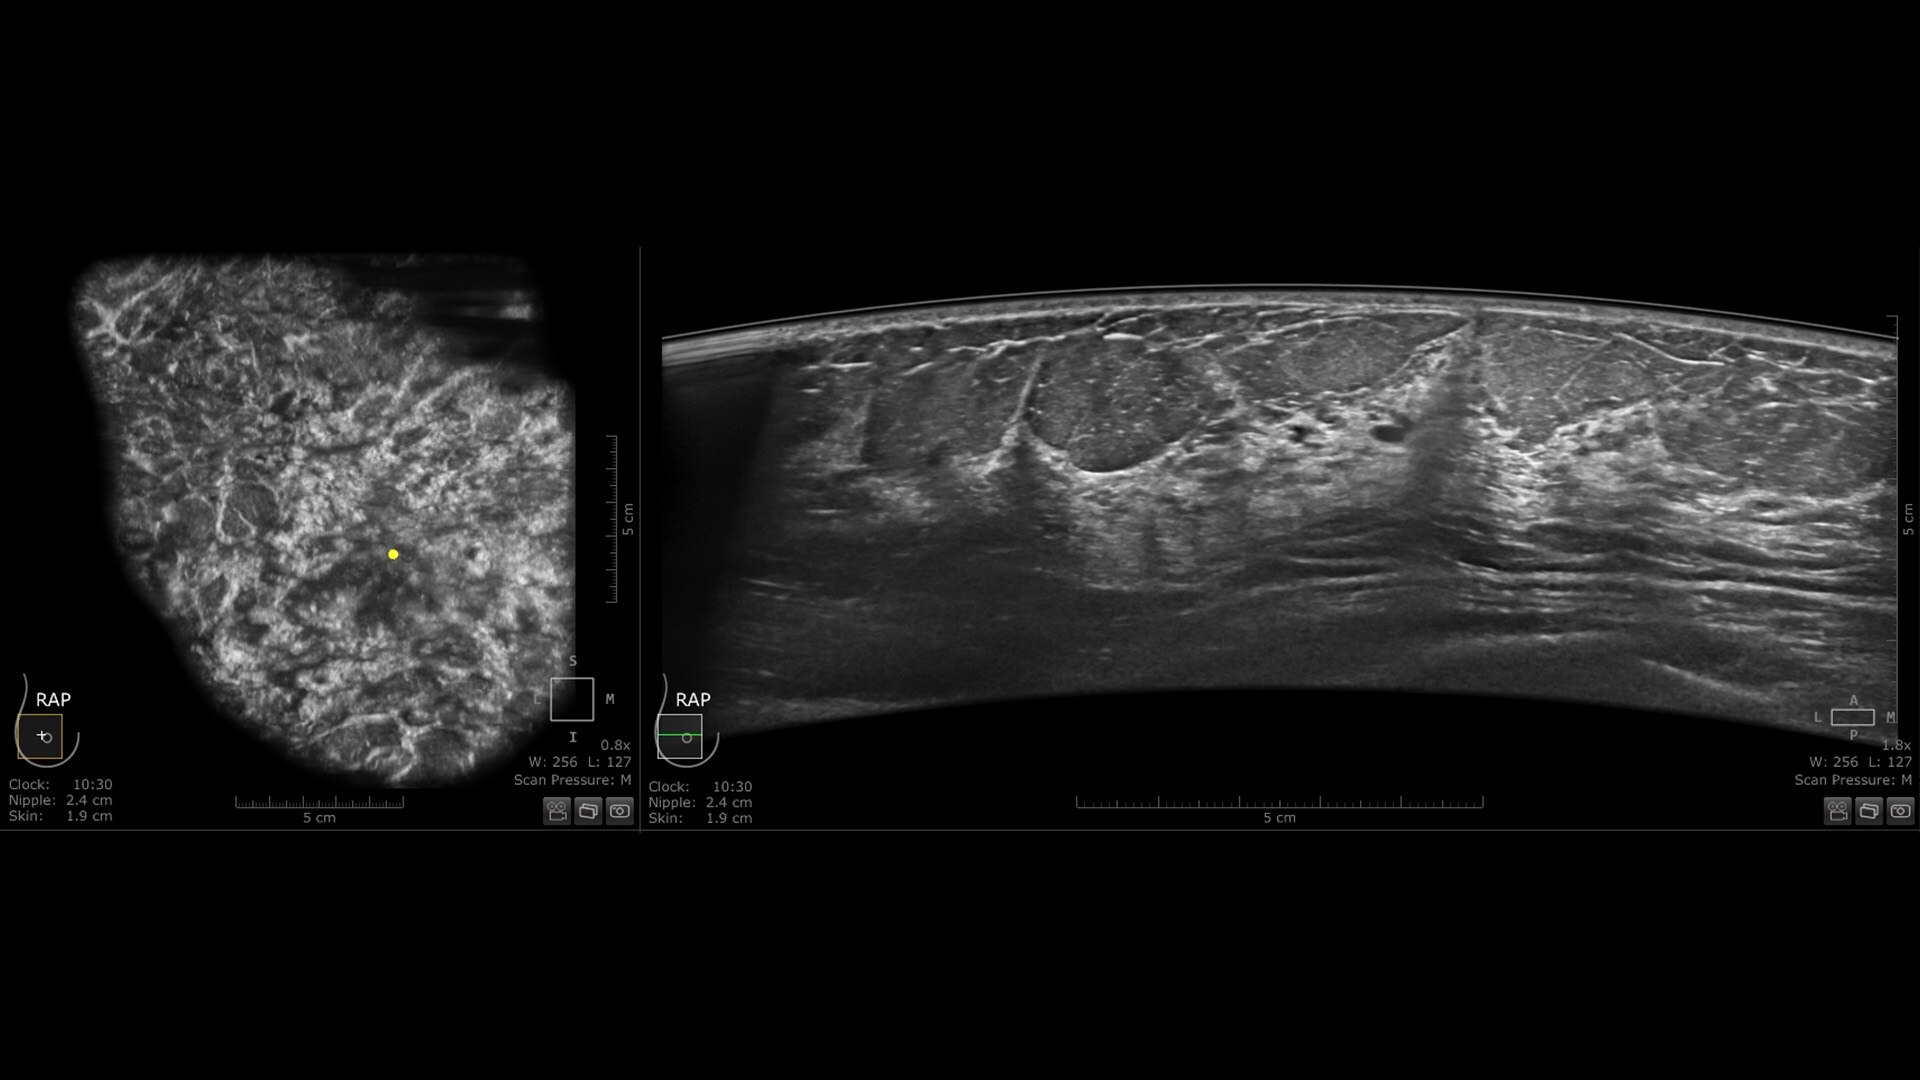

The latest innovation in breast ultrasound

The Invenia ABUS Premium is designed for high patient throughput and extraordinary image quality to provide a great level of confidence. With its innovative design, it’s easy to use, reproducible, user-independent, standardized and allows reading anywhere.

Screening

Exact lesion localization and double reading capability empower ABUS in early detection

Virtual rescans and multiplanar readings of the entire breast support case management

Planning

Offers a 3D view of the entire breast for precise and effective therapy planning

Monitoring

Compare reproducible ABUS volumes to priors to help monitor therapy response